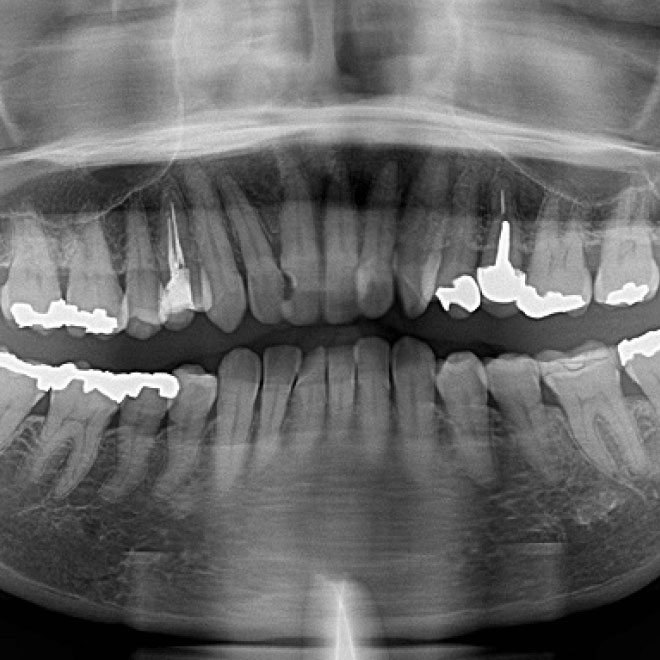

検査

レントゲンや口腔内写真、歯周病検査などお口の中の状態をきちんと検査し、どんなトラブルが起こっているのかを調べます。

治療の説明

検査結果をもとにお口の状態やどのように治療していくのかを説明いたします。レントゲンや口腔内写真を用いてわかりやすくお伝えします。